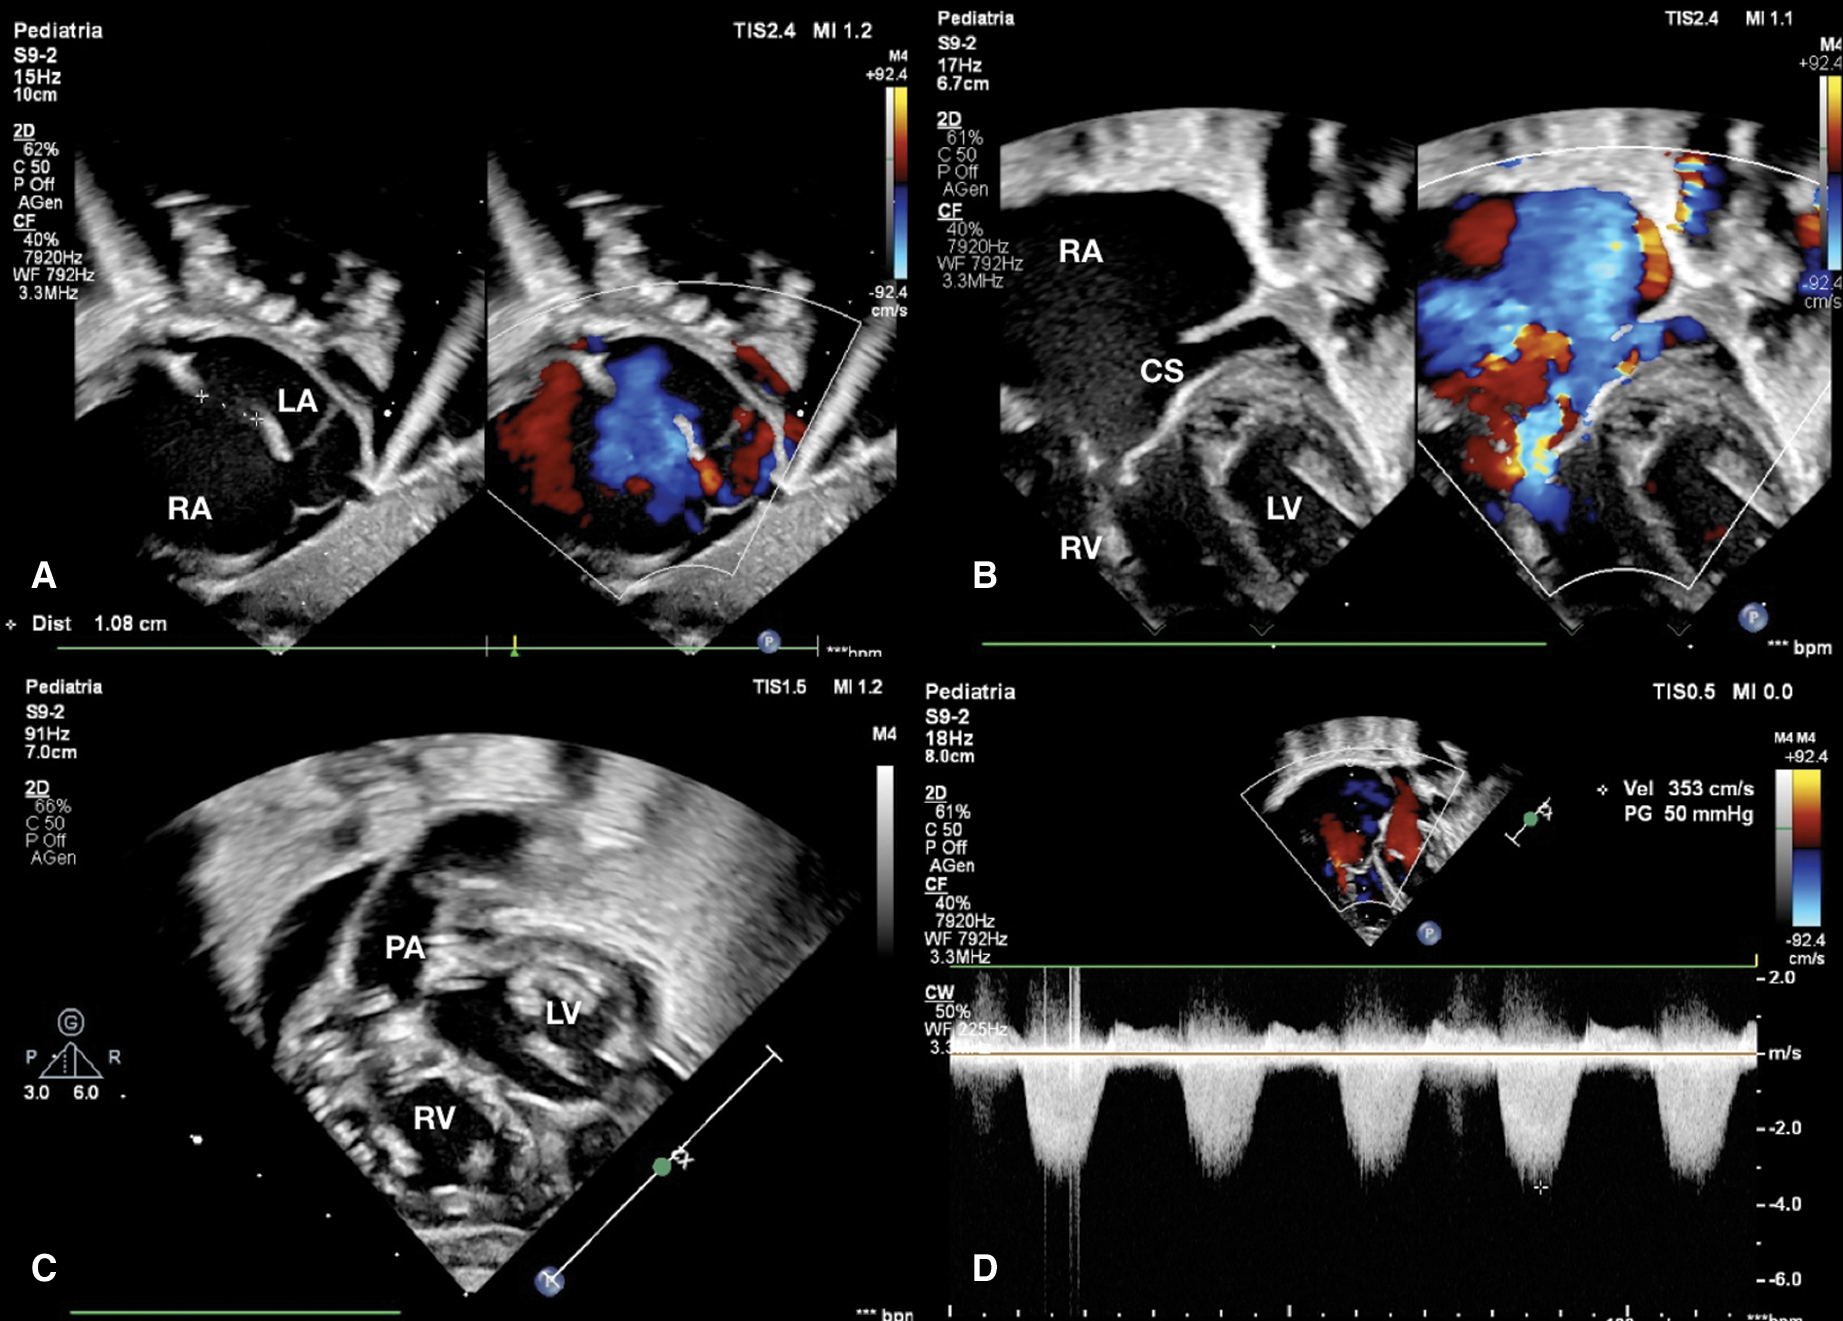

Echocardiography evaluation revealed tricuspid valve dysplasia with severe regurgitation and functional pulmonary valve atresia with intact ventricular septum. The massive tricuspid regurgitation was associated with enlarged right atrium (RA) (Fig. 1), without anterograde flow from right ventricle (RV) to pulmonary valve, resulting in a functional PA with reversal flow in the large patent ductus arteriosus (PDA) (Fig. 2) and pericardial effusion.

Figure 1: (A) Subcostal view shows expanded right atrium and atrial septal defect of 1.08 cm with right to left shunt. (B) Apical view shows severe tricuspid regurgitation and dilated coronary sinus for persistent left superior caval vein. (C) Ventricle short axis subcostal view shows atrioventricular valves and right outflow tract. (D) CW Doppler through tricuspid valve estimates a right ventricle pressure of 50 mmHg. CS coronary sinus, LA left atrium, LV left ventricle, PA pulmonary artery, RA right atrium, RV right ventricle